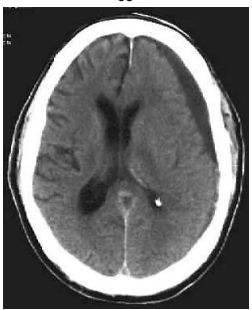

Senhor Liberato Tavares, 77 anos, comparece à emergência médica, trazido por

filho. Evoluindo nas últimas semanas com letargia e confusão mental. Portador de

hipertensão arterial sistêmica, hipotireoidismo e diabetes mellitus tipo 2, em uso

regular de medicações e acompanhamento com clínico assistente. Há relato do

filho de episódios prévios de tontura ao se levantar e TCE (traumatismo crânio

encefálico) repetidos nos últimos meses, tendo último evento conhecido de ocorrência há 30 dias. Realizada tomografia em urgência abaixo:

FONTE: https://emedicine.medscape.com/article/247472-overview?form=fpf, acesso em: jun. 2024